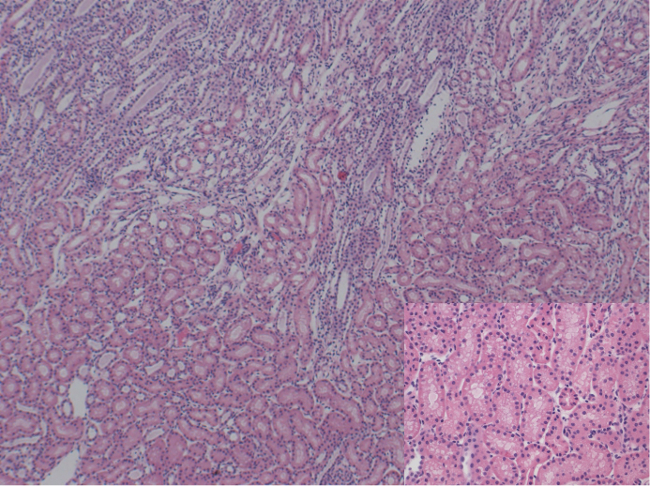

Hourly measurements of venous and arterial pO2 reveal the metabolic activity of the kidney. The oxygen consumption was calculated using the equation ((pO2art – pO2ven) x flow / weight) (Figure 6) 14. During the perfusion pH, HCO3, and electrolytes are stable without requiring interventions (Figures 7 - 10). Real-time AST and lactate measurements serve to monitor cellular damage. No increase of parameters of cell injury is detected during the NEVKP period (Figures 11 and 12). The osmolarity of the perfusion solution is stable (Figure 13). Histological assessment reveals minor changes (Figure 14 - 16).

Figure 14: Histology (H&E). 50X / 200X magnification of corticomedullary junction showing mild tubular vacuolization. No signs of necrosis. Please click here to view a larger version of this figure.